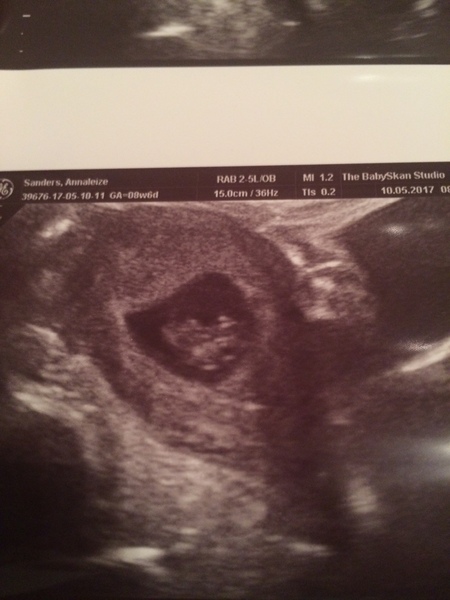

Lovely scan zaberwocky! Really baby like Grin got to wait a week and a couple of days for the next one. SO impatient!

@Zaber, what a lovely scan pic xxx

Haha zaber I've had the nipple situation too! Your scan pic is lovely - definitely looking baby-like now :)

Had an early scan today and so so pleased. Put me back a few days but couldn't care less as she said all looks perfect with the heartbeat ❤️

Lovely scan pic annie Smile

Annie that's a lovely scan, glad all is well.